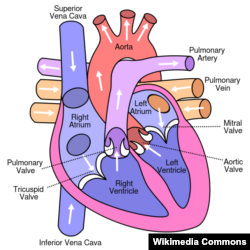

Tim là một cái máy bơm tự động. Tim bên phải đem máu nghèo oxy (đã dùng rồi, máu đen đem về từ ngoại biên qua các tĩnh mạch) lên phổi để nhận oxy từ không khí được hít vào. Tim bên trái bơm máu chứa nhiều oxy ( máu đỏ, oxygenated blood) đi nuôi các bộ phận cơ thể (kể cả trái tim). Mạch máu lớn đi từ tim trái là động mạch chủ (aorta), hình dáng tựa như cán cây dù: phần nằm trong lồng ngực gọi là động mạch chủ ngực (thoracic aorta) từ đó xuất phát những nhánh động mạch đi lên cổ và đầu và hai cánh tay; có ba đoạn, một đoạn đi lên gọi là ascending aorta, đoạn cong, ngang gọi là aortic arch (hay transverse aortic arch, cung động mạch chủ ), đoạn đi xuống gọi là descending aorta. Khi động mạch chủ đi xuống phía bụng, thì chúng ta gọi là động mạch chủ bụng (abdominal aorta), từ đó đâm những nhánh nuôi các bộ phận quan trọng như ruột, gan, thận và chạy xuống hai chân. Lúc tuổi già thì vách động mạch cũng yếu đi, cũng như do tác dụng của áp huyết cao (hypertension), hay do xơ vữa động mạch (atherosclerosis, do quá nhiều mỡ trong máu), hay do bẩm sinh, di truyền, cấu trúc vách động mạch không bình thường (vd: Marfan Syndrome), động mạch chủ sẽ nở to, phình ra (đường kính tăng, dilation of the aorta), vách động mạch chẻ ra làm đôi (aortic dissection) tạo nên một "lòng, ruột giả" (false lumen) càng lúc càng lớn và nghẹt lòng của mạch máu và đe doạ bể, và với thời gian, đến một mức giãn nở nào đó. (Tương tự như một ruột bánh xe đạp có thể phình to và đe doạ bể, vỡ ra nếu:

Những vùng nở to ra của động mạch chủ gọi là phình động mạch chủ ( aortic aneurysm, AA) thường xảy ra ở khúc bụng (AAA, abdominal aortic aneurysm), nhưng cũng có thể xảy ra trong ngực (thoracic aortic aneurysm), tuỳ theo mà chúng ta gọi tên mô tả loại aneurysm liên hệ.